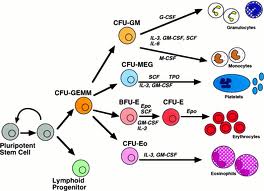

Che cos’è l’ematopoiesi L’ematopoiesi è il processo principale che avviene nel midollo osseo. Si tratta di un processo di differenziazione progressiva di una cellula staminale “multipotente” in distinte linee: Mieloide; Eritroide; Piastrinopoietica; Linfoide. L’ematopoiesi è...